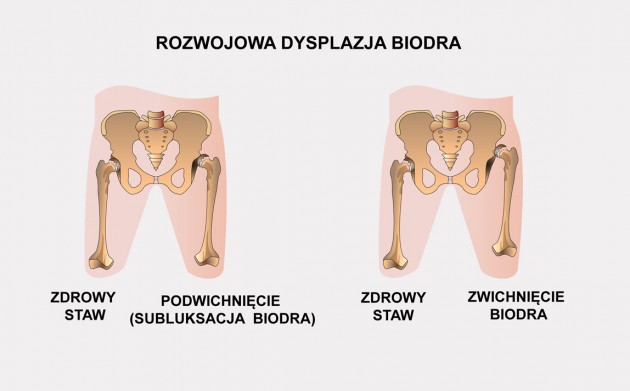

Dysplazja i zwichnięcie stawu biodrowego u dorosłych

Staw biodrowy to największy staw kulisty panewkowy u człowieka. Jest on stabilizowany za pomocą więzadeł, ścięgien i torebki stawowej. Staw biodrowy tworzy wypukła główka kości udowej oraz wklęsła panewka miednicy, które pokryte są gładką powierzchnią stawową. Dzięki temu, ruch w stawie odbywa się w sposób płynny i bezbolesny. Obrąbek panewkowy odpowiada za utrzymanie mazi stawowej oraz jest naturalną granicą stawu biodrowego.

Dysplazja stawu biodrowego oznacza, że panewka ma nieodpowiedni kształt, przez co nie jest w stanie prawidłowo „objąć“ główki kości udowej. Powoduje to dużą niestabilność i bolesność stawu, a także asymetrię ruchów.

Pierwszym objawem dysplazji bioder u osób dorosłych jest właśnie bolesność stawu (szczególnie podczas wzmożonych aktywności), a także utykanie. Rzadziej obserwujemy charakterystyczny dźwięk „przeskakiwania” w trakcie ruchu.

W medycynie wyróżniamy 6 typów dysplazji stawów biodrowych, które rozróżniamy w zależności od zaawansowania procesu chorobowego oraz czasu jego powstania1:

- Dysplazja bioder

- Rozwojowe zwichnięcie stawu biodrowego (DDH)

- Zwichnięcie biodra

- Rozwojowa dysplazja stawu biodrowego (DDH)

- Dysplazja panewki stawu biodrowego

- Wrodzone zwichnięcie stawu biodrowego (CDH)

u 29-letniej kobiety.

Nieleczone zwichnięcie bądź dysplazja stawu biodrowego prowadzą do zaawansowanych zmian zwyrodnieniowych, a w rezultacie nawet do kalectwa!